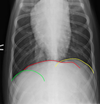

green

right crus

yellow

left crus

red

diaphragmatic cupola

red

diaphragmatic cupola